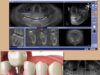

Однако факт остается фактом: иногда, к сожалению, наши естественные зубы уже не могут оставаться на своем месте, например, из-за слишком обширного кариеса и/или перелома корней зубов, и поэтому должны быть заменены как можно скорее. Восстановить полную функциональность при жевании и избежать, как мы сказали, смещения остальных зубов и последующего повреждения. В этом случае зубной имплантат с немедленной или отсроченной нагрузкой является решением, гарантирующим отличные показатели успеха и долгосрочные результаты, естественно, в тех случаях, когда есть показания к этому типу терапевтической альтернативы: на самом деле это необходимо предварительно оценить количество и качество остаточной кости и, если этого недостаточно, подумать о реконструкции кости для увеличения эстетического результата и срока службы имплантатов.

Каковы этапы хирургической процедуры установки имплантатов?

Хирургическая установка зубных имплантатов выполняется быстро и выполняется под местной анестезией в течение нескольких минут.